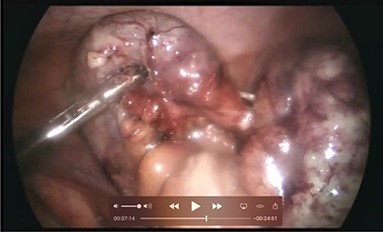

A 66-year-old male patient who had undergone bilateral blepharoplasty 3 days earlier was referred to our acute care surgical service with a 24-hour history of increasing right lower quadrant pain accompanied by nausea, vomiting and anorexia. Clinically he was found to be afebrile with a soft abdomen and focal tenderness at McBurney’s point. Significant laboratory investigations revealed a leukocytosis of 13.0. A CT scan of the abdomen confirmed the diagnosis of appendicitis with an impacted appendicolith at the appendicular outlet and a number of additional appendicoliths distributed along the length of the appendicular lumen (Figs 1–2). The patient was surgically consented for a laparoscopic appendicectomy with intraoperative video recording. At laparoscopy an inflamed and focally necrotic appendix was located coiled over the cecum (Figs 3–4). The appendectomy was completed without complication, and the specimen longitudinally transected in the operating room prior to pathological submission. This revealed four appendicoliths within the lumen, all measuring over 5 mm at their smallest diameter (Fig. 5). Pathology confirmed acute suppurative appendicitis with transmural necrosis, with the appendicoliths described as faeculent in origin. The patient’s post-operative recovery was uneventful.

Intraoperative picture demonstrating the inflamed and coiled appendix with signs of transmural necrosis.